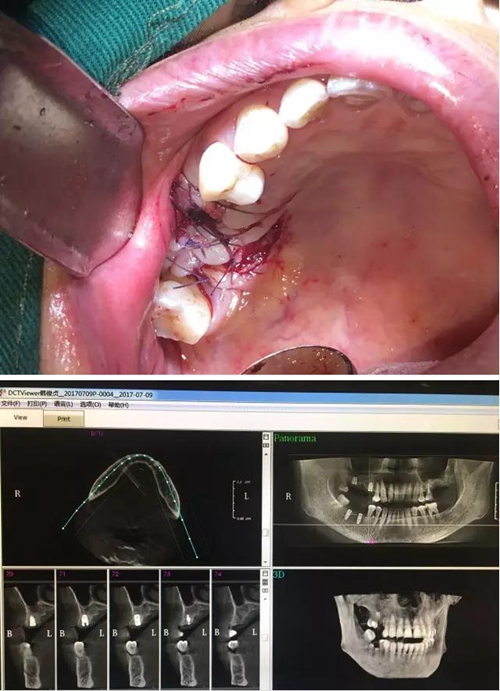

【病例分享】?jī)?nèi)提,用自體骨柱,不用骨粉

1.jpg